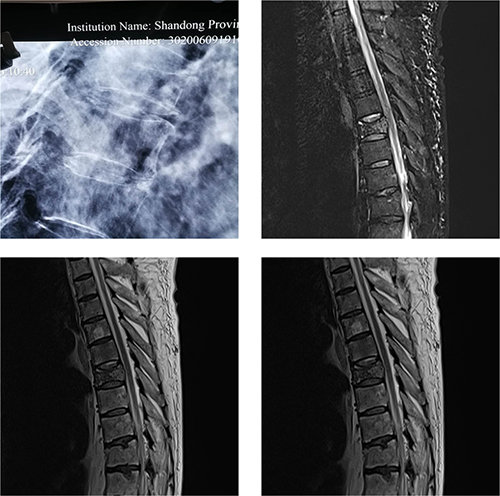

术前患者影像学图片

患者车某某,男,64岁。不慎扭伤腰背部,突发疼痛,遂至当地医院就诊,经CT检查显示患者T8压缩性骨折、T11陈旧性骨折。除此之外,当地医院检查发现,患者同时患有严重心衰,心功能IV级;苔藓8年;骨髓异常增生综合症3年,长期使用强尼松治疗导致严重的骨质疏松症状等多种疾病。屋漏偏逢连夜雨,患者胸椎骨折疼痛严重,咳痰不畅,导致坠积性肺炎持续加重,连续多天高烧不退,最高体温达40℃。

创伤急诊外科老年创伤骨科亚专业治疗小组在组长王甫主任医师带领下,立即组织全院会诊。重症医学科、心内科、呼吸科、血液科、皮肤科和麻醉科等科室共同讨论,患者同时患有压缩性骨折、陈旧性骨折、重度骨质疏松症、MDS、慢性心功能衰竭(心功能IV级)、室间隔膜部瘤并肺动脉高压、坠积性肺炎、双上肢静脉炎、苔藓等九大疾病,手术风险极高。